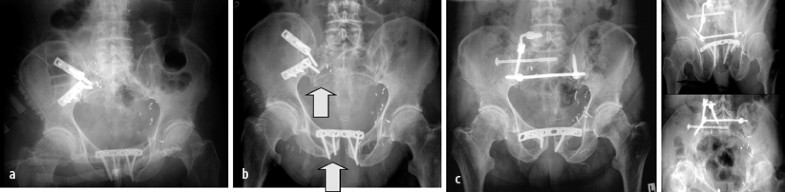

Bei dem in Fall 4 (Abb. 4, Abb. 6) geschilderten Beispiel jedoch kam es durch Sturz aus dem Bett zur Redislokation der Montage und zusätzlich zu einer additiven Sakrumfraktur entlang der Sakrumschrauben, was eine erneute operative Versorgung erforderlich machte (s. unten).

Fall 4, a postoperatives Versorgungsbild, b Redislokation der Montage, Fraktur des Sakrums periimplantär, c Implantatentfernung, Re-ORIF und erneute Embolisation von A.-iliaca-interna-Ästen, weitere Erläuterungen s. Kasuistik

Fall 4

Bei dem 62 Jahre alten männlichen Patient mit einer AO-Fraktur 61C1.2 wurde mittels Kontrastmittel-CT eine erhebliche aktive Blutung im Extraperitonealraum nachgewiesen, die trotz Beckenzwinge und Anlage eines supraazetabulären Fixateur externe persistierte. Bei der somit erforderlichen operativen Versorgung wurden die aktiv blutenden Äste der A. iliaca interna („coiling“) embolisiert (Abb. 4) und eine innere Osteosynthese vorgenommen.

Im Rahmen eines Durchgangssyndroms kam es 3 Tage nach der definitiven Versorgung zum Sturz aus dem Bett und dabei zur Redislokation der Montage sowie einer additiven Fraktur entlang der Sakrumschrauben. Die konsekutive Rekonstruktion beinhaltete eine Sakrum übergreifende Reosteosynthese nach Entfernung der ventralen unilateral das Iliosakralgelenk übergreifenden Implantate, eine Distraktionsspondylodese und eine neuerliche Stabilisierung der Symphysenruptur. Ferner war eine abermalige angiographische Embolisation erforderlich, da sich nach Reinstabilität eine neuerliche arterielle Blutung aus A.-iliaca-interna-Ästen manifestierte (Abb. 6).